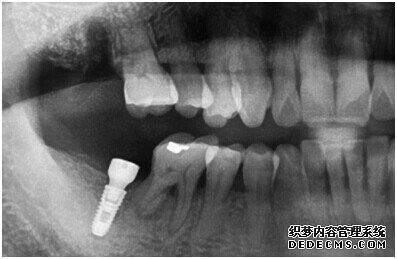

由CT片检查来看,刘女士口腔健康环境还是很好的,牙槽骨也适合种植牙的条件,而且由我们最后一颗牙是非常重要的,经过专家的建议和详细解释了原因之后,刘女士选择了美国百康种植牙。